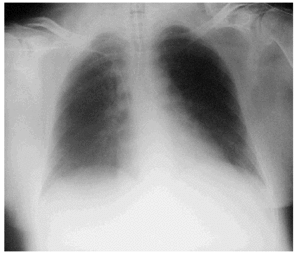

La paciente acudió al Servicio de Urgencias por vómitos y malestar general, que se atribuyeron a la medicación anti-VIH por lo que se decidió suspenderla. La analítica realizada no mostró alteración alguna, por lo que fue dada de alta al domicilio. En esa oportunidad no se le realizó gasometría. Cuarenta y ocho horas más tarde ingresó en la unidad de cuidados intensivos (UCI) por bajo nivel de conciencia (escala de coma de Glasgow [GCS], 7 puntos), hipotensión (90/60 mmHg) e importante aumento del trabajo respiratorio por lo que se la intuba y conecta a la ventilación mecánica (FiO2 40% y presión positiva a final de la espiración [PEEP] 0). En la exploración destacaban una hepatomegalia y edemas. En la analítica de sangre se encontraron los siguientes hallazgos: pH, 6,77; PaCO2, 21 mmHg; PaO2, 62 mmHg; HCO3, 4 mEq/l; exceso de bases, 31,6 mEq/l; hemoglobina, 13 g/dl; leucocitos, 25.400/ml (83% neutrófilos); plaquetas, 169.000/ml; urea, 50 mg/dl; creatinina, 2,7 mg/dl; Na+, 155 mEq/l; K+, 2,2 mEq/l; glucosa, 33 mg/dl; bilirrubina, 0,8 mg/dl; GOT, 68 U/l; GPT, 30 U/l; tasa de protrombina, 44%; fibrinógeno, 144 mg/dl; CK, 397 U/l; CK-MB, 123 U/l; troponina I, 0,15 ng/ml; etanol, 5 mg/dl; amilasa, 1.493 U/l; ácido láctico, 145,6 mmol/l (rango normal 4,5-19,8); CD4+, 95; carga viral, 199 copias/ml. La radiografía de tórax mostraba atelectasias segmentarias bibasales (fig. 1). En la tomografía computarizada de abdomen se apreciaba hepatomegalia hipodensa, esteatosis y mínima cantidad de líquido libre en ambas gotieras y en la pelvis; el páncreas, los riñones, el bazo y las suprarrenales eran normales (fig. 2).

Figura 1. Radiografía de tórax tras la intubación y la conexión a ventilación mecánica. Se observan áreas de atelectasia bibasales. El corazón es de tamaño normal.